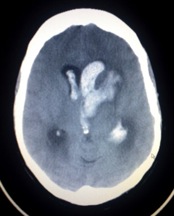

The image below is that of a patient who suffered a hemorrhagic stroke. Note that both intraparenchymal and intraventricular bleeding are present.

The move file below is of cadaver 33512. Begin by looking at the head in its entirety (time 25-40), comparing its appearance to the still CT image above. Notice that from time 30-40 blood can be seen in both lateral ventricles (especially the inferior horns at time 35, K12 and N12), the cerebral parenchyma (time 32, M10), and the cerebellum (time 35-40, L10). Now scan back up to the very top of the cranium (time 27-28). Notice at locations K10 and M10 that two holes have been drilled through the cranium and into each cerebral hemisphere. These were likely drilled as a final effort to drain the blood from the ventricles and relieve the pressure on the brain caused by the massive intracerebral hemorrhage.

Unlike ischemic stroke, hemorrhagic stroke results from intracranial bleeding. The pressure from an expanding intracranial hematoma compresses the brain, which mechanically distorts and injures brain tissue. Furthermore, the increased pressure being applied by the hematoma can occlude arteries feeding affected areas of the brain, leading to ischemic injury as well. Hemorrhagic stroke is further broken down into several categories based on the type of intracranial bleed:

1. Intra-axial hemorrhage (blood inside the brain)

1. intraparenchymal hemorrhage (bleeding in the cerebral parenchyma)

2. intraventricular hemorrhage (bleeding in the ventricles)